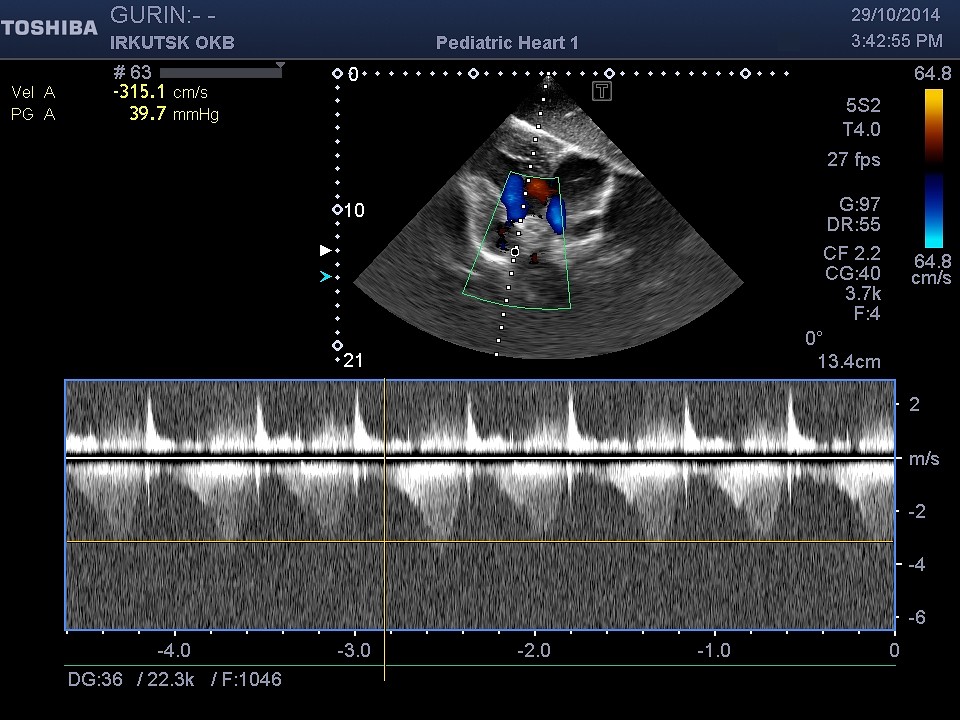

"Единственная надежда осталась у меня на Вашу помощь . Моего ребеночка зовут ГУРИН АЛЕКСАНДР ЕВГЕНЬЕВИЧ 07.02.2008 Г/Р,проживаем мы в городе Братске, Иркутской области, ул. Войнов-интернационалистов д13-кв.38., меня зовут Гурина Светлана Александровна, вот и вся наша семья!! Экология в нашем городе все больше и больше влияет на наше здоровье, не прошло и мимо нас!!!! У моего сыночка страшный диагноз : ВПС, единый желудочек сердца, транспозиция магистральных сосудов, ДМПП вторичный и совсем недавно выявлена еще и недостаточность митрального клапана 3ст.Легочная гипертензия, которая не дает моему сыну нормально жить!!!!!Диагноз нам поставили на четвертом месяце после рождения, но подозрение на порок были уже на второй день его жизни! хотя всю беременность я отходила без каких либо отклонений! Каждый год мы планово посещаем областной центр в городе Иркутске и вот только сейчас врачи выявили желание прооперировать его , но при больших страхах. В моей жизни не было слишком много счастливых моментов, но никогда прежде я не была так счастлива когда у меня появился мой малыш!Узнав о клинике в Германии, чьи врачи делают действительно чудеса, я обратилась за консультацией именно к ним, зная что в России таких деток оперировали не много, и что чаще всего результат заканчивался трагично! На мое письмо они ответили сразу, и как только они получили результаты последних обследований, то естественно согласились, понимая, что наша ситуация не из лучших! Но к сожалению таких средств мне самой никогда не найти, даже если все продать, хотя продавать то мне собственно и нечего!!!Разве что свою жизнь в обмен на жизнь своего ребенка! Я не работаю, так как не один работодатель меня не хочет держать, сыночек потому что очень часто болеет, из целой недели мы ходим в садик максимум три дня! а садик для него это единственное место, где он может пообщаться со своими сверстниками! Поэтому сижу дома по уходу за ребенком - инвалидом!Весь доход составляет 21850 рублей в месяц, при том условии что я снимаю квартиру за 10000рублей,так как своей не имею.